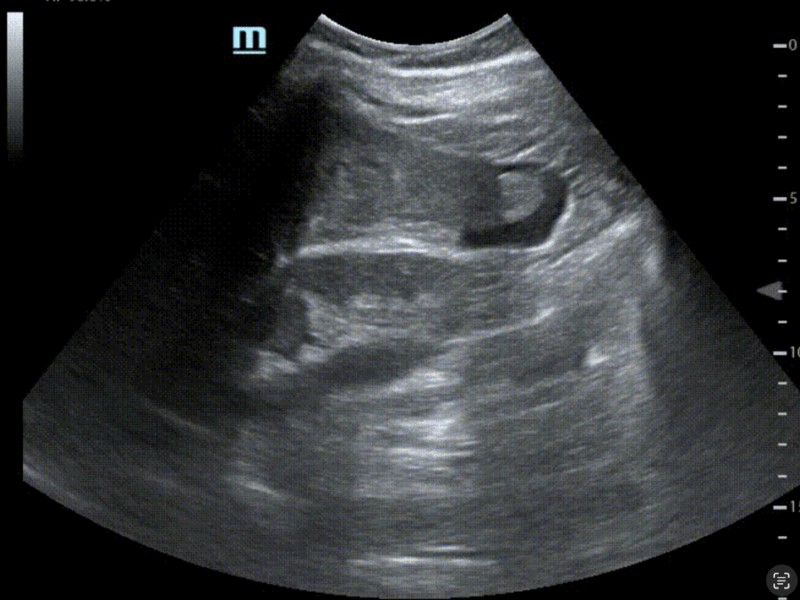

EchoFirst et l’innovation

Nous avons l’honneur de vous annoncer que EchoFirst fait désormais partie du pôle TES, en temps qu’organisme de formation d’échographie. Fort de son approche innovante dans la formation d’échographie et de ses racines Normandes, EchoFirst fait désormais parti intégrante du pôle TES.